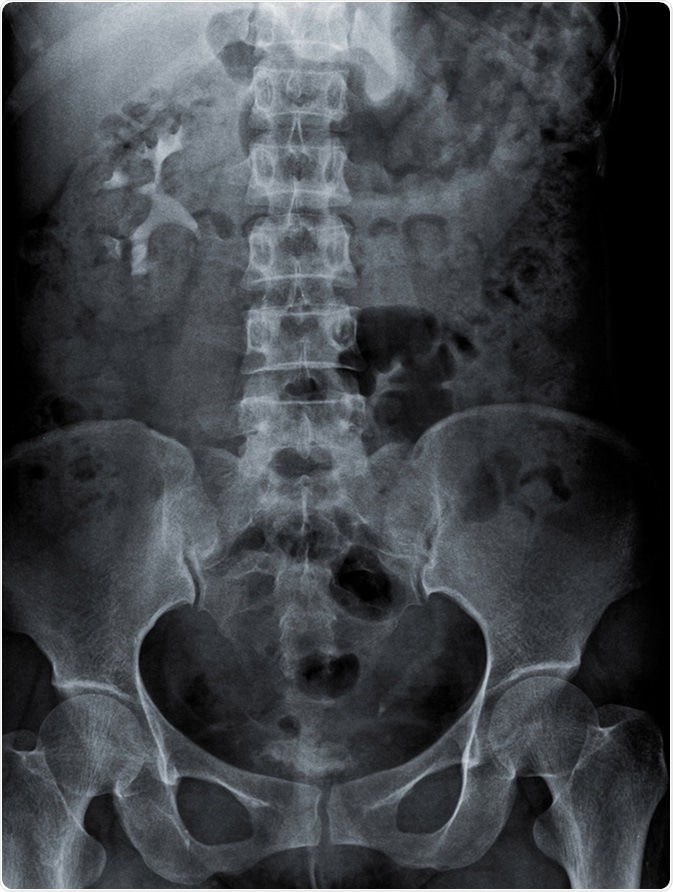

Radiography of kidney with intravenous Contrast at one hour. Image Credit: kaling2100 / Shutterstock

KUB stands for kidney, ureter and bladder. A KUB radiograph is an X-ray performed for the purpose of examining the urinary system and its surrounding structures.

The region covered by a KUB radiograph includes the area that spans the superior poles of the kidneys downwards to the pubic symphysis. This radiograph, like all X-rays, employs the use of external electromagnetic beams to acquire images of internal tissues and organs.